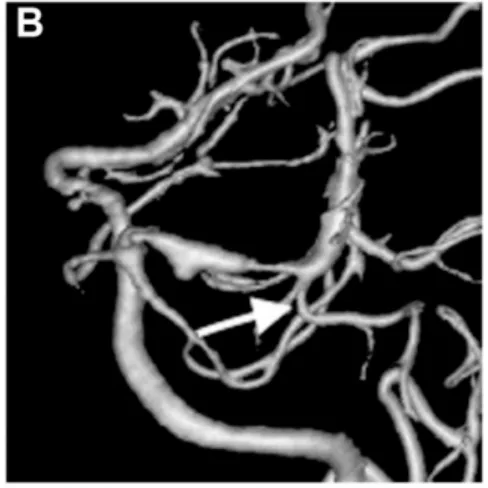

出血后18天血管造影显示左侧P1-P段扩张伴狭窄特征,颞后动脉自狭窄病变远端发出(箭头标注)。

出血后第18天,患者病情稳定后,医疗团队实施脑血管造影检查。检查结果揭示左侧大脑后动脉P1-P2段存在异常扩张伴狭窄表现——符合夹层动脉瘤的典型影像学特征。